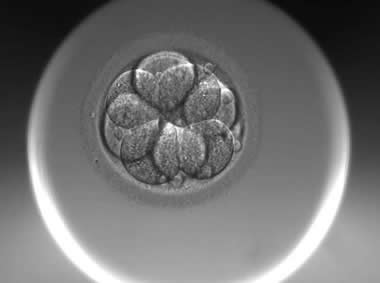

下面视频是胚胎在时差培养箱中培养至D3的整个过程,图片是D3(第68小时)的卵裂期胚胎图,本文D3胚胎评价是以D3时间点图片的形态学为依据,胚胎评级如下:

| Ⅱa级:该枚D3胚胎为9细胞,碎片不超过10%,因此评级为Ⅱa级。 | |